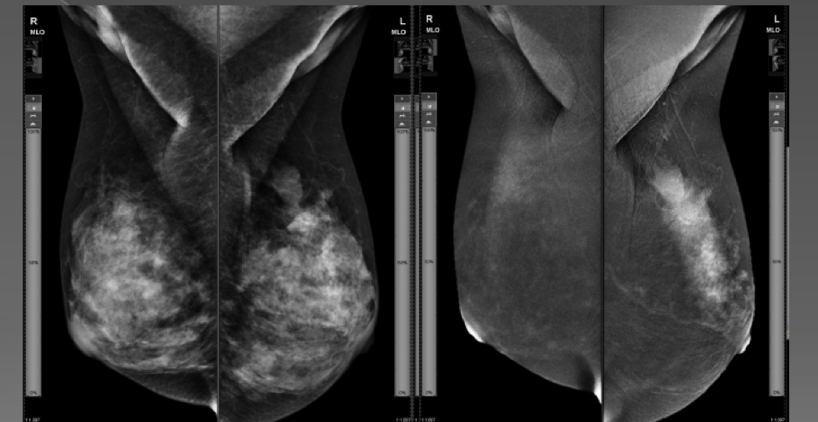

5.Mamografi: Memenin X ışınları kullanarak görüntülenmesidir. Görüntü kalitesi ve detayları bilgisayarlı sistemler yardımıyla arttırılmıştır.

Tarama (screening) mamografileri semptom olmadan önce yıllık düzenli yapılan görüntülemelerdir.

Tanısal (diagnostik) mamografiler memede veya koltuk atında bir belirti varlığında yapılan testlerdir. Tarama mamografilerine göre daha detaylı yapılan incelemelerdir. Tarama mamografileri 10 ile 20 dk arası sürerken tanısal incelemeler çok daha uzun sürebilir.

Her iki mamografi çekiminde de düşük doz - X - ışınları kullanılır. Standart dijital 2 boyutlu (2dimensional-2D) veya 3 boyutlu (3D) olarak çekimler yapılabilir. 3 boyutlu olan mamografi çekimine tomosentez de denir.

Tarama (screening) mamografileri meme kanserine bağlı ölümleri azaltmak için geliştirilmiş testlerdir. Standart olarak her bir memeden iki yön olmak üzere toplamda 4 poz görüntü alınır. Bu görüntüleri değerlendiren radyolog eğer gerekli görürse ilave çekimler isteyebilir.

Tomosentez veya 3D mamografi dijital mamografinin en yeni türüdür. Memedeki küçük normal dışı bulguların daha kolay görülebilmesine imkân verir. Memeye ait çok sayıda ince kesit görüntüler (yaklaşık her memeden 90-120 adet) alınır ve en son birleştirilerek tek bir görüntü oluşturulur. Standart dijital 2D mamografiye göre tomosentez incelemede hastaları geri çağırma oranlarında azalma ve kanser saptama oranlarında artış olduğu kanıtlanmıştır. Bu yüzden meme taramalarında 3D mamografi (tomosentez ) inceleme önerilmektedir.